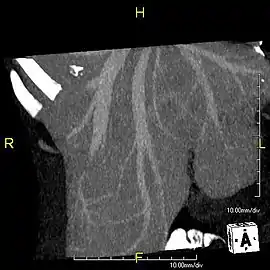

Axial CT image showing anomalous hepatic veins coursing on the liver's subcapsular anterior surface[66]

Axial CT image showing anomalous hepatic veins coursing on the liver's subcapsular anterior surface[66] Maximum intensity projection (MIP) CT image as viewed anteriorly showing the anomalous hepatic veins coursing on the anterior surface of the liver

Maximum intensity projection (MIP) CT image as viewed anteriorly showing the anomalous hepatic veins coursing on the anterior surface of the liver Lateral MIP view in the same patient as previous image

Lateral MIP view in the same patient as previous image A CT scan in which the liver and portal vein are shown